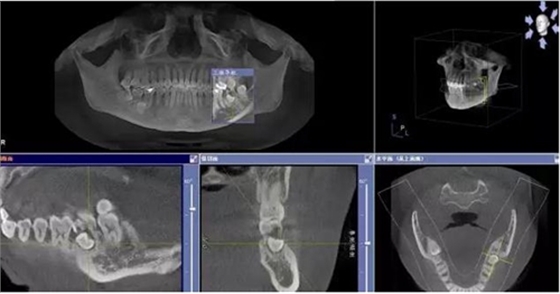

患者、申xx、女、40歲,主訴:左側(cè)下頜后牙牙齦紅腫不適數(shù)月。??茩z查:37合面有一開髓孔。髓腔內(nèi)有一暫封小棉球,探針?biāo)枨坏撞砍鲅?,疑為在外院治療?dǎo)致底穿。x線片檢查:37頰側(cè)齦下有一枚多生牙,多生牙壓迫頰側(cè)牙根及牙體組織大量吸收。

圖1.術(shù)前的CBCT檢查:37頰側(cè)部分牙根被完全壓迫吸收。